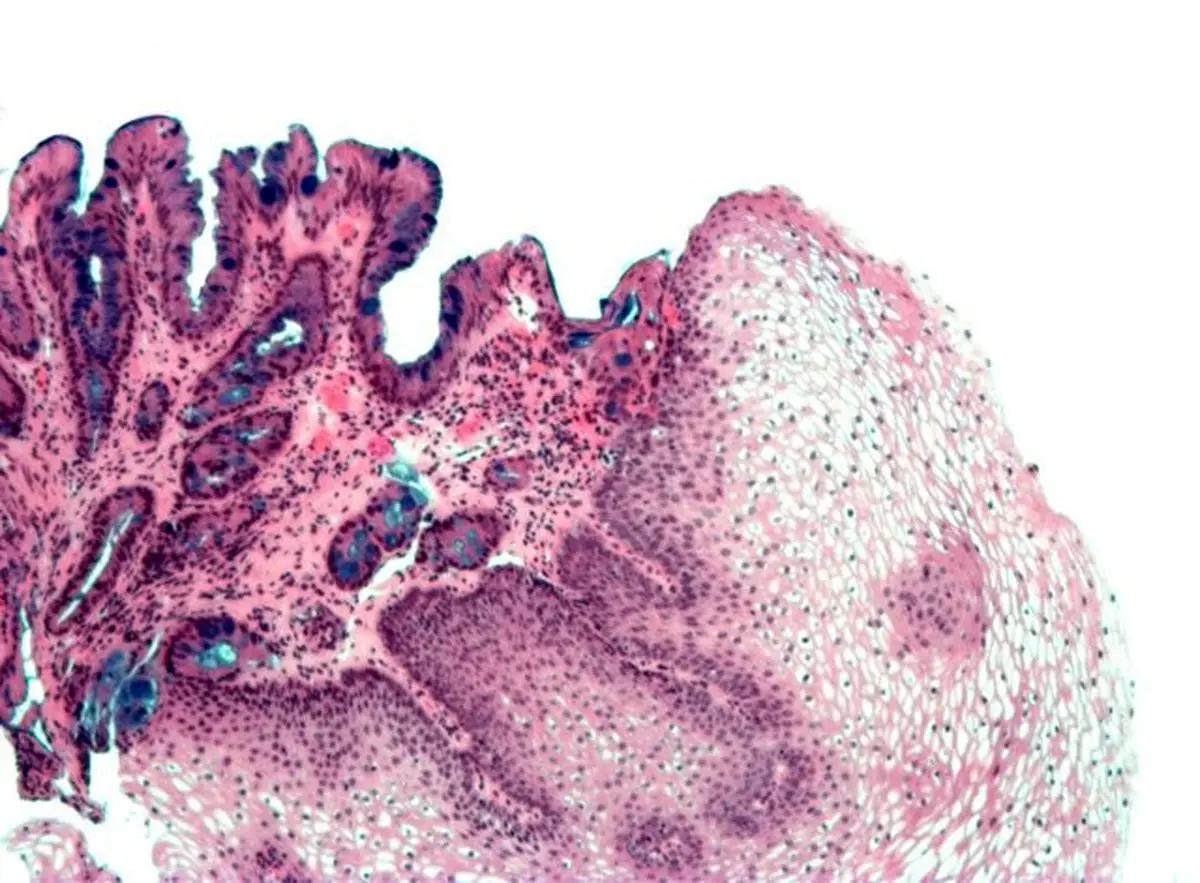

مری بارت، یک بیماری پیش سرطانی است که طی آن، بافت پوششی مری تغییر می‌یابد و به بافتی مشابه بافت پوششی معده تبدیل می‌شود.

افراد مبتلا به بیماری مری بارت، بین ۳۰ تا ۴۰ برابر بیش از دیگران در معرض خطر ابتلا به سرطان مری قرار می‌گیرند.